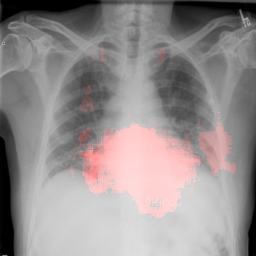

4.2.1 Cardiomegaly Localization

The localization of abnormalities in cardiomegaly examples are shown in Fig. 7. Here, of the image area is shown which has the highest sensitivity. It can be observed from the figures that the network is indeed most sensitive to the region where the heart is larger than a normal heart. We have performed this experiment on cardiomegaly and normal images and found this localization to be consistent for most examples. There is not much functional difference between a normal and cardiomegaly example other than the fact that the heart in cardiomegaly is larger than a normal heart. Given the fact that the normal images could also have various size of heart depending on the age or physical attributes of a patient, we found this level of localization sensitivity to be remarkable. Also interesting is the fact that the standard rule based features like CTR and CTAR take into account the relative size of heart and lung to determine if there is cardiomegaly present or not. In the DCN localization experiment, we see counter-intuitively that most of the signals contributing to the softmax score are coming from the heart only. This means that there are characteristic features in the shape of the heart and its surrounding regions that alone is sufficient to detect cardiomegaly. The lung and its relative size are probably less important features when trying to detect cardiomegaly. This observation is counterintuitive and needs to be explored further in future work.

8 Additional Examples of Localization

In this section we show more examples of localization. Few localization samples are shown in Fig. 11. It can be observed that, in the CXRs with Cardiomegaly (Fig. 11(a) and (b)) a fine localization around the heart is observed. In the normal CXRs (Fig. 11(c) and (d)) such localization is not observed. Rather the lowest probabilities are spread out in the CXR image. It is interesting to note that, the localization algorithm gets low probability where the heart is enlarged during cardiomegaly, but the proportion is small compared to the localization in other areas of normal CXRs. In order to observe the performance of the heat map we computed histograms of heat maps of each of the 100 CXRs in the test set for Cardiomegaly detection and average histograms are shown in Fig. 11(e) and (f) for CXRs with Cardiomegaly and normal CXRs, respectively. It is to be noted that, the histograms include both success and failure cases. It can be observed that, for CXRs with Cardiomegaly the classifier is highly sensitive toward Cardiomegaly detection even under occlusion. This indicates that, the classifier primarily looks for local features in a CXR instead of some feature that is spread out in the entire CXR. However, the classifier is not sensitive toward normal CXRs under occlusion. Rather, the probabilities are spread out in the probability spectrum. After that, we analyzed the failure cases where the classifier is unable to classify the image correctly. Two such examples of failure cases are shown in Fig. 12. The localized CXR shown in Fig. 12(a) contains Cardiomegaly whereas the classifier detects it as normal. However, the localization shows that it localizes around heart quite well despite the in accurate classification. On the other hand, Fig. 12(b) shows an example of normal image which has been classified as Cardiomegaly by the classifier. There is stronger localization around the hear that that is observed for normal images as in Fig. 11(c) and (d), however, like those images the localization is spread out.